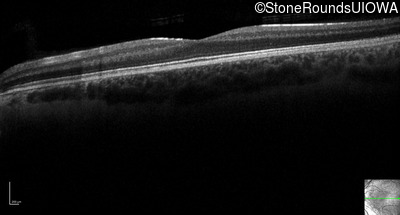

Optical Coherence Tomography - Right - 10/160 sc

Exemplar